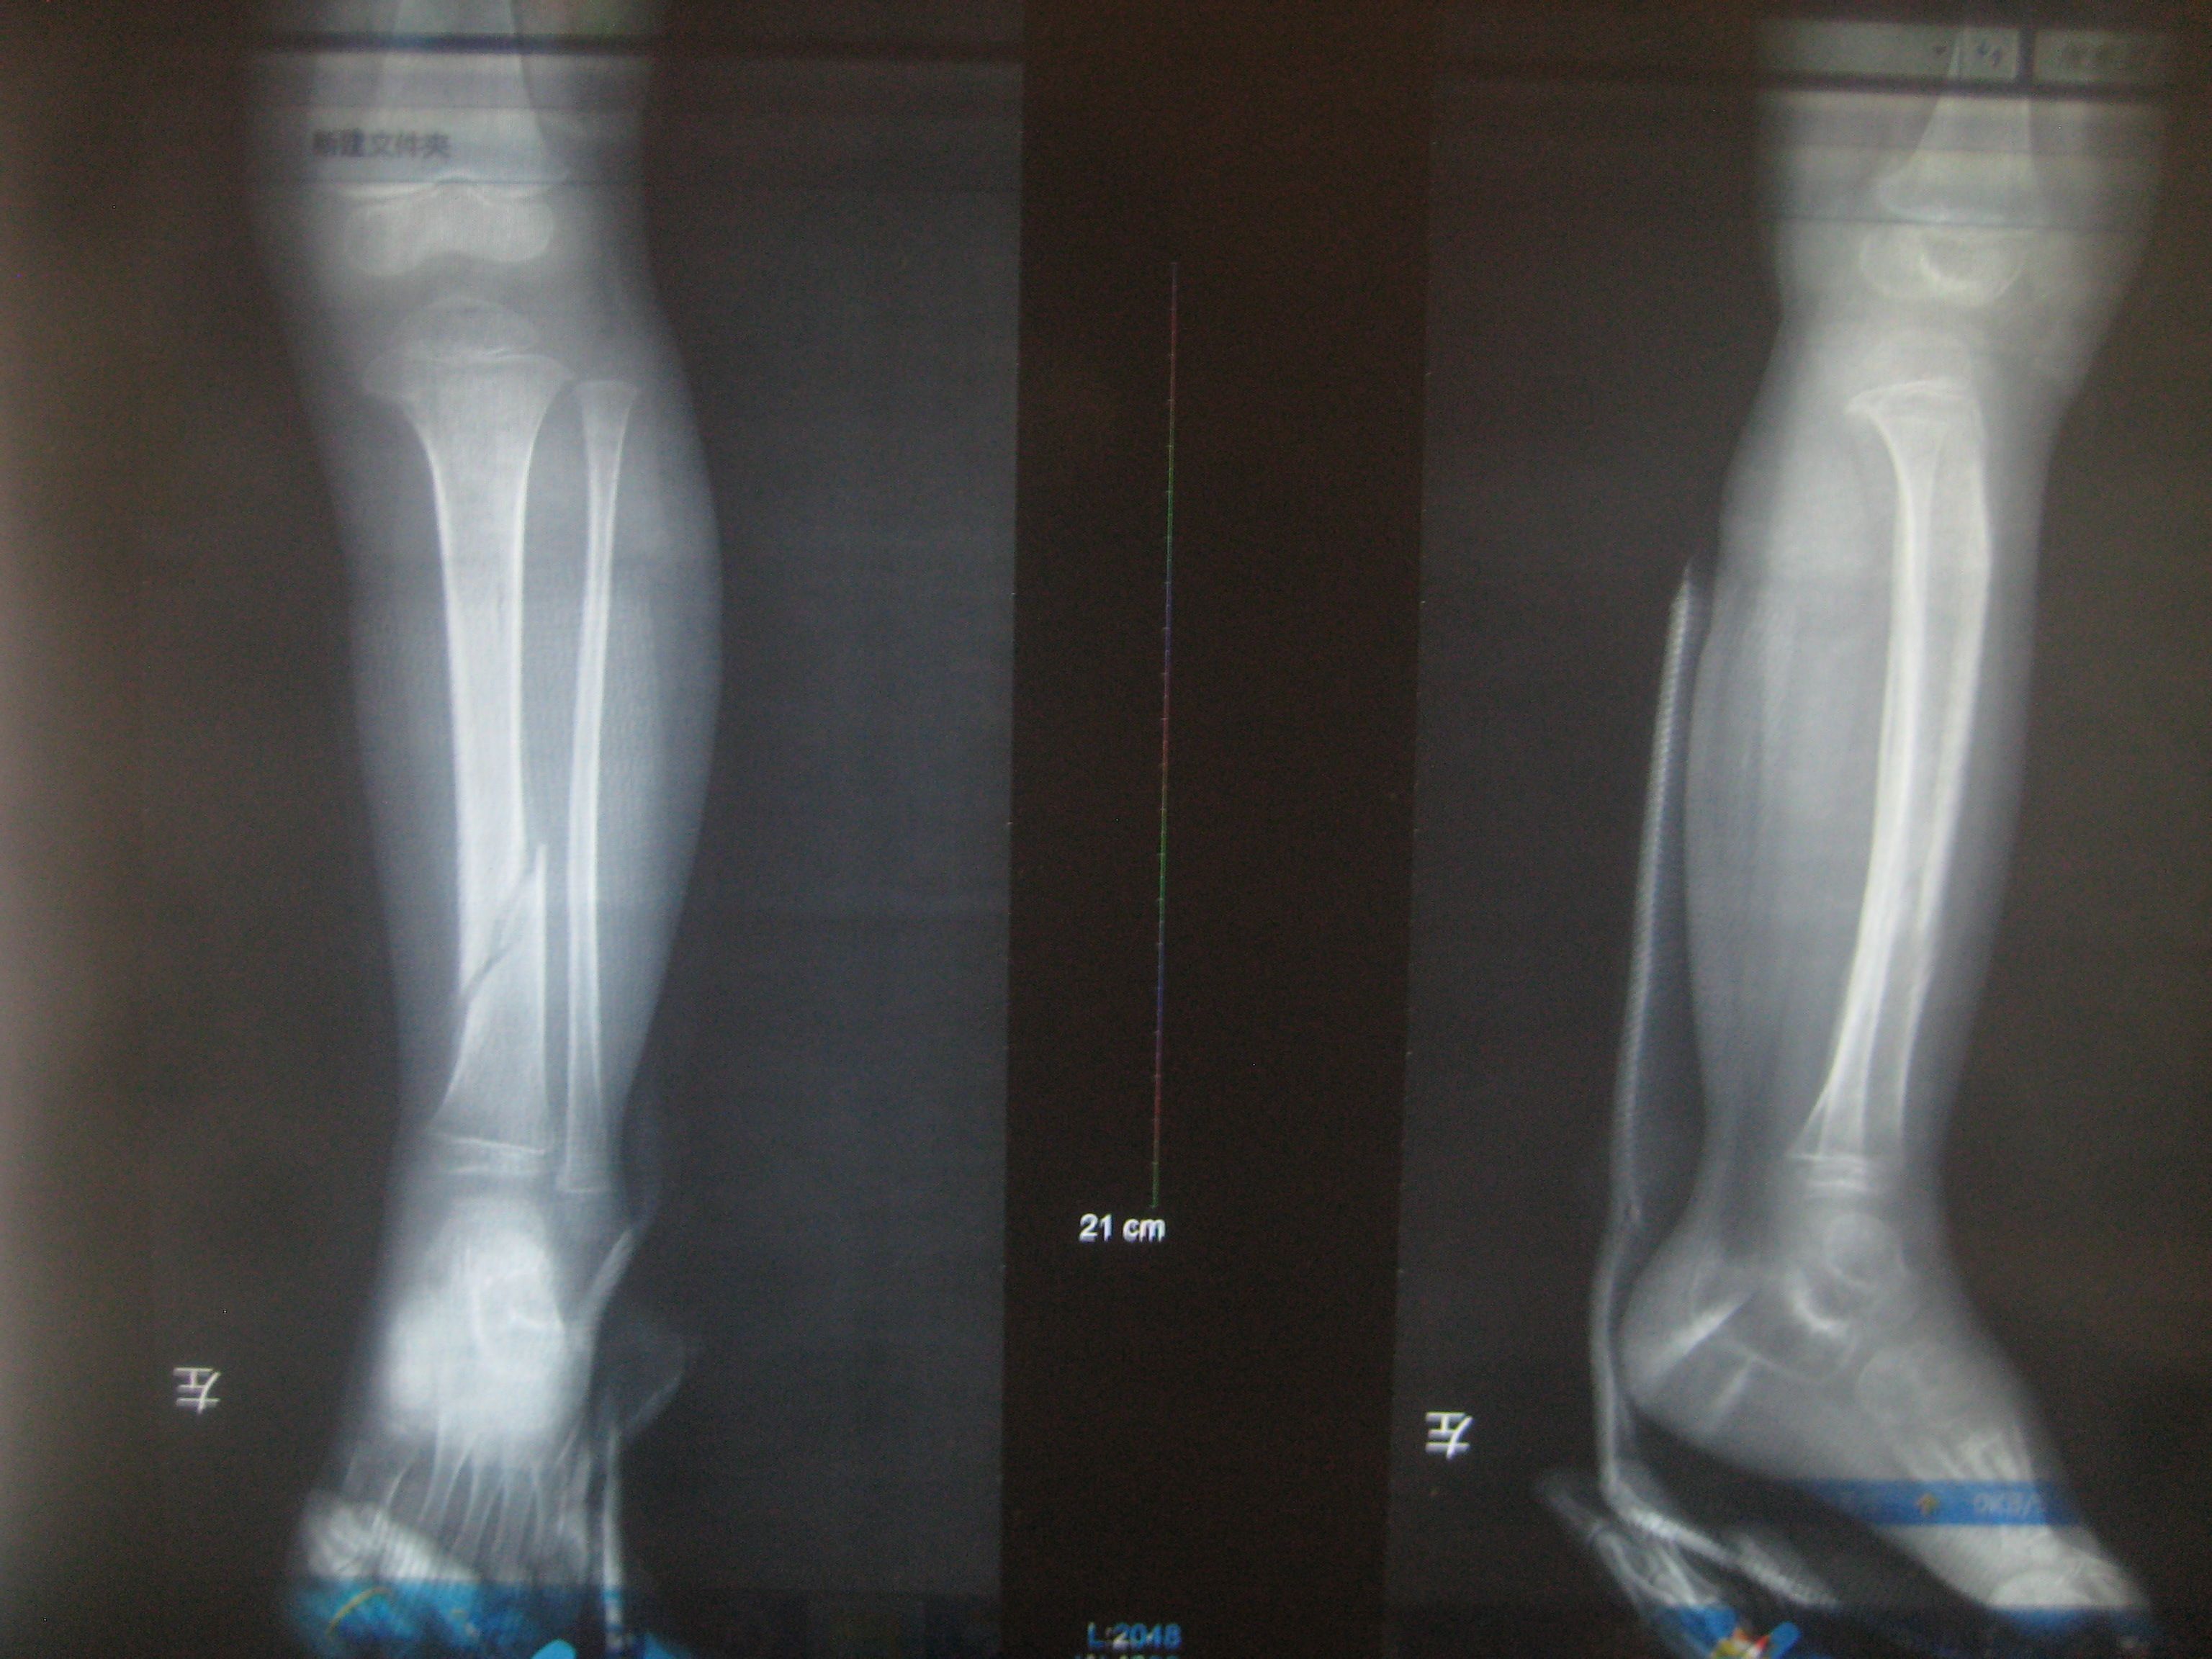

小孩左胫骨下段螺旋形骨折,X光复查对位不是很准,对以后行走有影响吗,会不会出现后遗症呢 点击展开 母婴用户244640837 2014-05-23 14:57 为您推荐: 其他回答 病情分析: 您好,这个情况最好还是再矫正一下,因为这个有点成角移位 指导意见: 最好去医院正骨科看看,需要进行矫正,然后石膏或夹板固定。并且还需要定期复查。当然如果条件允许,最好通过手术复位内固定,因为这种斜型的骨折不太稳定 万俟傲薇_MtoA 2014-05-23 15:01 相关问题 2岁小儿左胫骨远端斜行骨折有后遗症吗 什么时候可以走路 宝宝右胫骨骨折一星期复查断端略移位正常吗 小孩右胫骨骨折打了石膏15天后复查还是老样子,现在老是跪着玩,影响治疗不